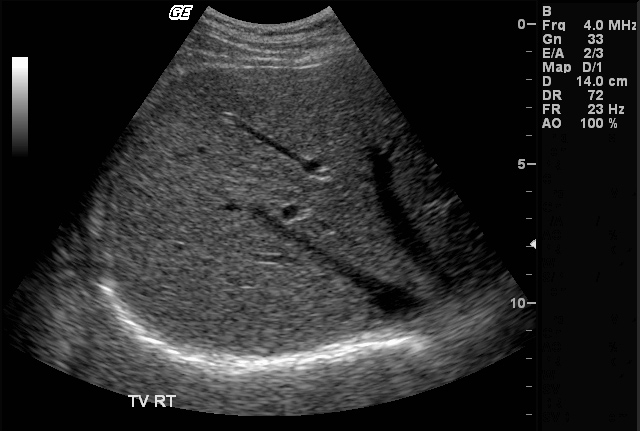

Сонограммы и УЗИ почек